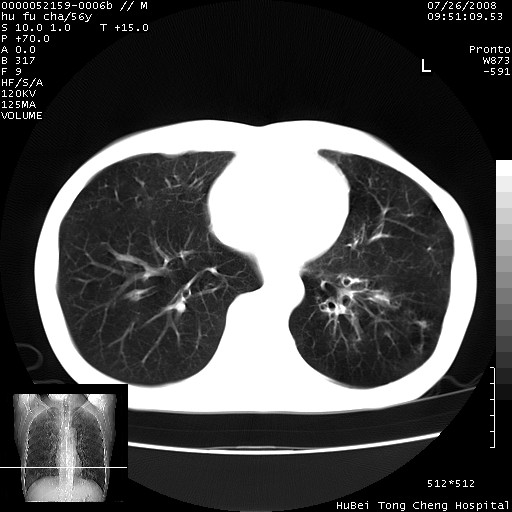

以下是引用zsl6918在2008-8-25 22:47:00的发言:[br]胸骨,胸椎及肋骨均可见多发转移表现,肝内低密度结节不除外转移。原发灶可能在右肺。双侧可见支扩表现。